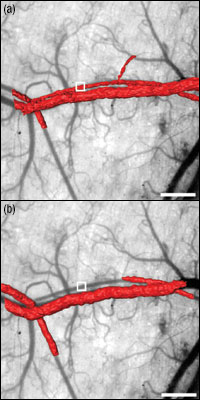

Figure 1.1 Three-dimensional rendered SS-OCT images of blood flow in mice whose vasculature has been exposed using a dorsal skinfold window chamber. Photosensitizers designed for two photon excitation were administered and the region denoted by the small white box in each frame was illuminated with 920 nm light (<3 mW). For the targeted blood vessel, blood flow is from left to right. Three-dimensional renderings of Doppler OCT images, in red, pretreatment (a) and post-treatment (b) demonstrate blood flow occlusion caused by two-photon excitation of the new photosensitizer. Renderings are overlaid on steromicroscope images taken pretreatment. Traditionally, single-photon excitation has been used in PDT techniques, but recently, the advantages of two-photon excitation (TPE) -- namely its quadratic dependence on light intensity and ability to allow deeper tissue penetration -- have made it a desirable choice for targeting specific treatment areas. Since two-photon excitation only occurs at the location where the two photons illuminate the same focal volume, this technique enables high spatial targeting of the treatment area. Recently, a group of researchers used a Thorlabs 1325 nm Swept Source OCT (SS-OCT) Imaging System to evaluate results from in vivo PDT treatment of anesthetized nude mice bearing dorsal skin windows. Using a photosensitizer that they designed for two-photon excitation, Collins and collaborators were able to induce blood vessel closure. After injecting the mice with 10 mg/kg of the photosensitizer, the volume of interest was irradiated with 920 nm light (300 fs, 90 MHz, 39 mW) for 15 minutes. 3D Doppler OCT images of the targeted vessel were acquired before and after two-photon excitation (See Figure 1.1). To construct these 3D images of the blood vessels, one thousand transverse scans were used to obtain an 83 μm x 83 μm image. By looking at the Doppler frequency shift induced by moving red blood cells, researchers were able to observe flow velocities as low as 100 μm/s. The results presented here show that SS-OCT imaging is capable of non-invasive 3D visualization of vasculature before and after two-photon PDT treatment. Such images were previously unavailable using confocal or stereomicroscopy techniques. In addition, the results demonstrate that two-photon PDT treatment is a viable choice for targeted occlusion of blood vessels. |